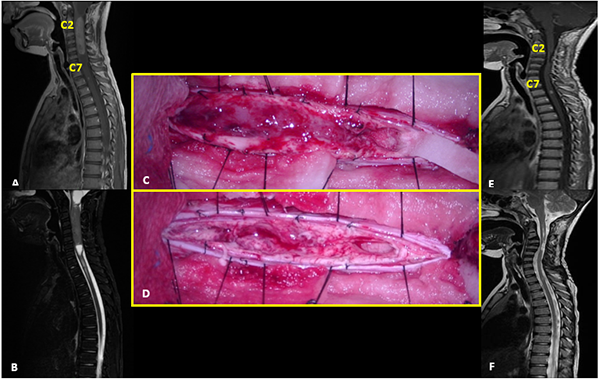

Paciente sexo masculino con NF2 que comienza a los 7 años con cervicalgia de 2 meses de evolución refractaria a analgésicos evidenciando en la RM un tumor intramedular cervical (C2-C7) con realce post contraste y el “signo del gorro” típico de ependimoma. Se realizó exéresis completa de la lesión demostrado en la RM control. El monitoreo intraoperatorio mostró caída de la onda D cercana al 50%. El McCormick postoperatorio inmediato fue grado 3. A los 6 meses de seguimiento con rehabilitación se evidenció mejoría clínica con McCormick grado 1. La anatomía patológica informó ependimoma clásico. Posteriormente el paciente evolucionó con progresión de su enfermedad de base, con lesiones intracreneales que requirieron tratamiento quirúrgico y radiocirugía. Casi 6 años después de la resección del ependimoma cervical, presentó recidiva local (C3-C4) y aumento considerable de una lesión a nivel de C1-C2 intra-extradural que se controlaba con imágenes seriadas. Se realizó la exéresis completa de ambas lesiones en un mismo acto quirúrgico, cuya anatomía patológica reveló schwannoma para el tumor extramedular y ependimoma clásico con Ki67 de 6% para la lesión intramedular. Como complicación alejada presentó dehiscencia de la herida, que requirió cierre quirúrgico (Figura 5).

Figura 5:

Ependimoma. A-B: RM prequirúrgica T1 con contraste y T2 cortes sagitales. C-D: Imágenes intraoperatoria pre y postresección. E-F: RM postquirúrgica T1 con contraste y T2 cortes sagitales.